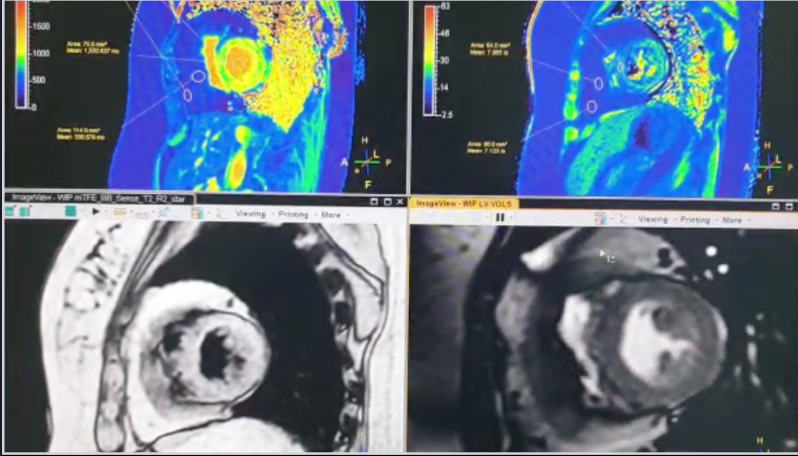

Thrombus, MaR (myocardium at risk) and IV contrast enhanced SSFP cines (CE-SSFP) in cardiac MRI.

It is preferable to do your cines pre-contrast for various reasons,.including, but not limited to, good CNR between myocardium & blood pool. However, doing CE-SSFP does have its advantages. Specifically for thrombus, the thrombus sticks out like a sore thumb and remains jet black on your cine images (as it would on your early gads too), especially if imaged not long after administration of the gadolinium chelate. I also find that CE-SSFP highlights MaR (myocardium at risk) quite well- in that areas at risk become hyperintense (due to the IV contrast) ...correlating to T2 imaging if it has been done well & is free of artefacts. Sometimes CE-SSFP shows up MaR quite well in areas that might not show any late enhancement- which is a good diagnostic indicator (in my view). In this example, I have done my long axis views (2 & 4 chambers) pre-contrast, but my SA post contrast- note the signal of the thrombus and the hyperintense areas of MaR on the CE-SSFP SA- correlating to areas of infarct on the LGE images. Thoughts anyone/everyone?